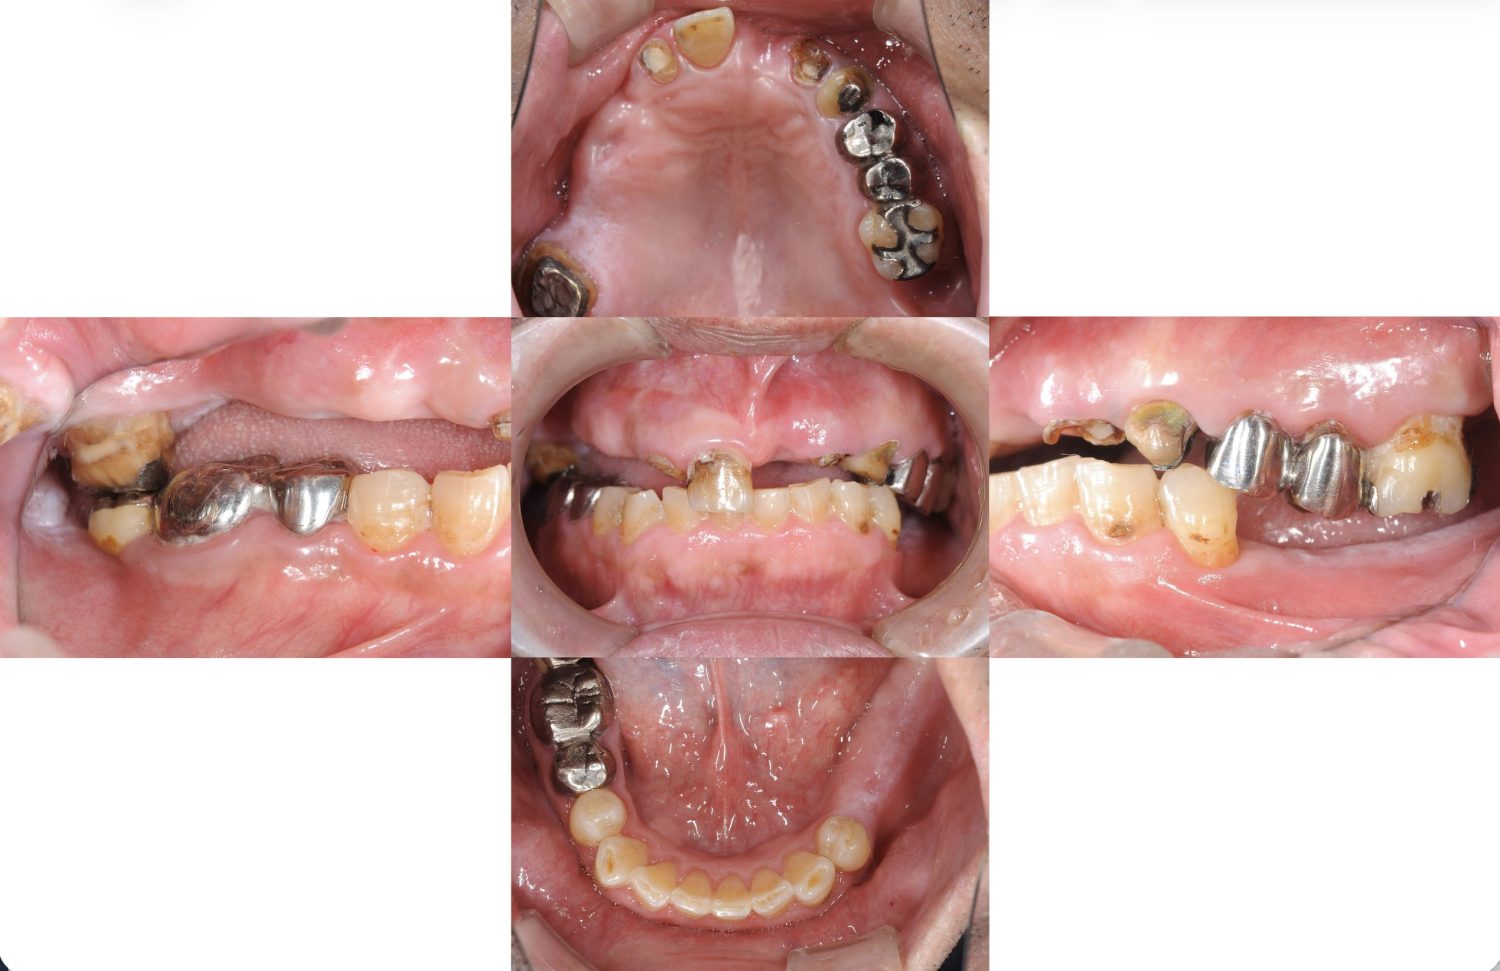

多数歯欠損のインプラント治療の症例(うえだ歯科)

上田大介(うえだ歯科)

症例詳細

| 主訴 | 歯がグラグラで噛むことができない。インプラントをして欲しい。 |

| 治療内容 | 歯周病で骨の吸収が重度で保存不能なため抜歯、仮の入れ歯を作り、6ヶ月の抜歯窩の治療の後に、インプラントのCTによる診査診断を行い、下顎に6本インプラント埋入と同時に仮歯を入れる。その後、上顎は8本のインプラント埋入と同時に仮歯を入れる。左右上6はソケットリフトによる上顎洞拳上術を行う。その後免荷期間6ヶ月待ってセラミックを用いた上部構造作製、装着しメンテナンスに移行する。 |

| 治療費 | 9,000,000円(税込) |

| 治療期間 | 2年3ヶ月 |

| 治療回数 | 90回 |

| 想定されたリスク | 重度の歯周病により無歯顎になったため、プラークコントロール不良による、術後のインプラント周囲炎が懸念される。歯冠の部分はセラミックなため欠ける可能性がある。 |